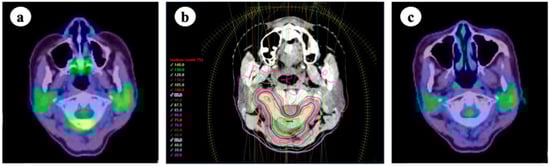

7. Stereotactic Body Radiotherapy for Oligometastases of Lymph Node